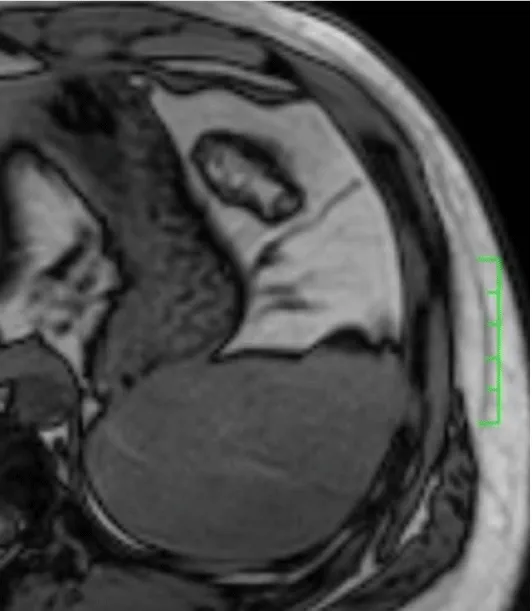

Solitary well-circumscribed masses were detected in all the five patients by ultrasound. One mass was of hypoecho, while the remaining masses were of hyperecho with posterior enhancement (Figure 1A). The maximum diameter ranged from 3.0 cm to 9.0 cm. At CT scanning, two masses appeared as hypodense (Figure 1B) and one was isodense (Figure 2A) to the normal spleenic parenchyma. In the two patients who received MR imaging, masses were isointensity at T1 weighted images (Figure 3A) and hypointensity with scattered sign void spots at T2 weighted images (Figure 3B). After intravenous injection of the contrast materials, all the five masses presented circle enhancement at arterial phase (Figure 3C and Figure 4A), while peripheral enhanced node was noted in one mass (Figure 2B). The circle enhancement persisted and radical line enhancement were observed at portal vein phase in 3 cases (Figure 1C) and progressive filling in was seen in two cases (Figure 2C). At delay phase of MR imaging, one lesion showed obvious enhancement with stellate low signal scar in the center comparing with surrounding splenic parenchyma (Figure 3D), while the other demonstrated central and circle enhancement to form a spoke-like appearance (Figure 4B). At delay enhanced CT scanning, two masses were isoattenuation to the surrounding splenic parenchyma (Figure 2D) and one lesion kept as hypoattenuation but with radial enhanced lines and enhanced circle to form a spoke-like appearance.

At pathological examination, all the masses were well demarcated on gross cut surface. A central stellate scar with peripheral interspersed dark brown nodules and the whitish intervening fibrous bands was noted to form spoke-like appearance (Figure 3E), which was well correlated with CT and MR imaging findings at enhancement. Microscopically, these angiomatoid nodules were surrounded by dense concentric collagen fibrous stroma and dispersed stromal cells with oval-to-spindle nuclei and scanty cytoplasm (Figure 3F). The abunden fibrous stroma may result in hypointensity at T2 weighted MR images. Hemosiderin was noted in the angiomatoid nodules (Figure 3G), which might contributed to signal void at T2 weighted MR images.

It usually affects middle-aged adults [6] and it is commonly found incidentally on radiographic imaging, or during operation for an unrelated condition. In present series, the patients are middle-aged adults without any related symptoms and the lesions were detected incidentally at routine ultrasound of health examinations. On ultrasound, manifestations of SANTs are vary widely from heterogeneous echo-texture with hyperechogenic, hypoechogenic, or isoechogenic appearing lesions, which are unspecific [7,8]. CT and MRI can show some characteristic features of SANTs, which include a solitary well demarcated mass with early peripheral enhancemant with radiating lines and progressive enhancement at the delay phase, and hypointens at T2 weighted MR images [2,3,5,9-13]. These features reflect the underlying pathological changes of scattered angiomatoid nodules separated and surrounded by sclerotic fibrotic stroma [10]. In present series, we also observed these characteristic features with well correlation to pathological findings. Circle and spoke-like enhancement can be contributed to fibrotic stroma surrounding and separating the angiomatoid nodules. The sclerotic fibrotic stroma may also result in isodense on CT, isointensity on T1 weighted images and hypointensity on T2 weighted images of MR imaging. The signal void spots at T2 weighted MR images have not been described at other literatures and may be contributed to hemosiderin deposition due to magnetic susceptibilty artifact.